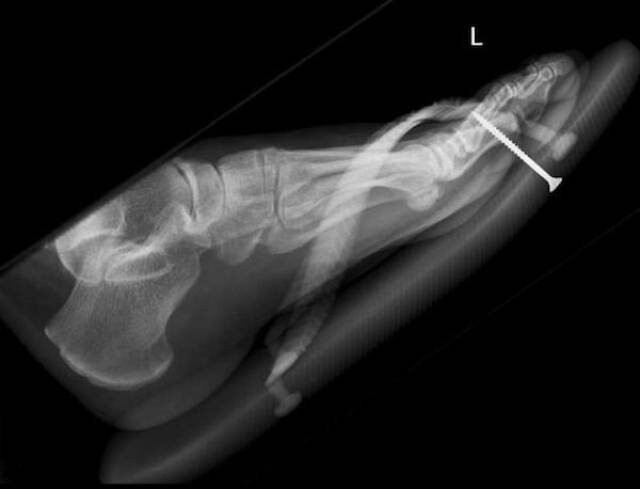

15. Модель Эйфелевой башни в руке